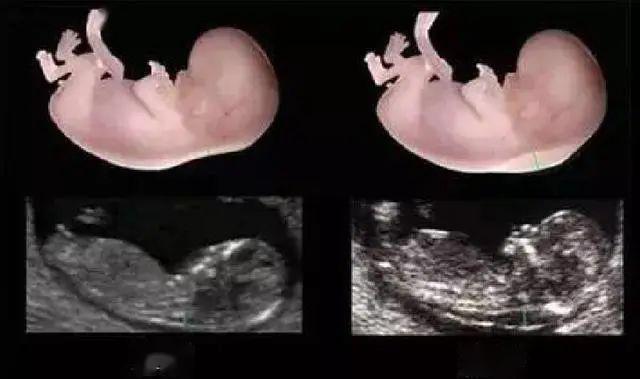

怀孕20~24周

孕中期系统筛查。即通常说的四维检查,这个时期是排查胎儿畸形的最佳时期,可以排查六大严重致死性畸形,对胎儿面部、神经系统、消化系统、泌尿系统以及其它系统的常见结构畸形做出筛查判断。这次检查也是5个阶段中最重要的一次超声检查,十分必要,耗时较长。